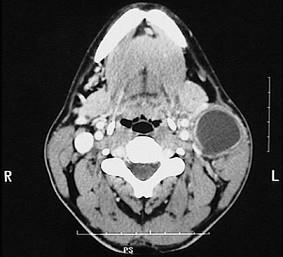

40岁女性,右上颈部包块发现5年,增长不明显。近3天发生上呼吸道感染,肿物突然增大,伴疼痛。检查见肿物位于胸锁乳突肌上1/3前缘,质软,有波动感,无搏动,体位试验阴性。CT 检查如图。最可能的诊断是 ( )

A海绵状血管瘤

B囊性水瘤

C鳃裂囊肿

D神经鞘瘤

E甲状舌管囊肿